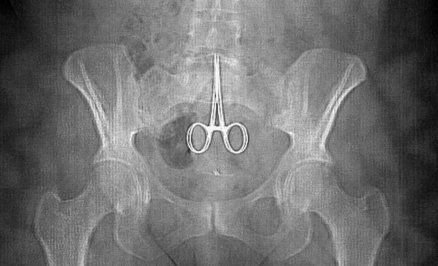

Below is a surgical intrument accidently left in a body after an operation.

scissors2